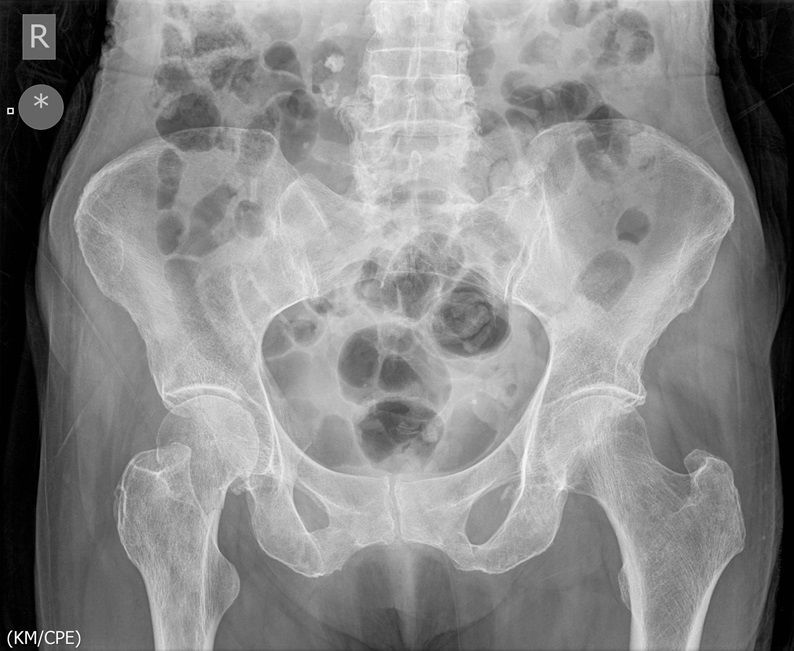

I was hoping you would partake in a study we are doing. We want to establish if there is any bias when deciding an operation based on the radiograph. We understand that the NICE guidelines state that the patient management for hip surgery should not be based on the radiographic findings; rather it should be based on defined criteria. However with that aside what we are requesting is that you look at the film + decide what operation either THR or Hemiarthroplasty. Click the dot + select answer.

Question 2

Question

Which operation would you perform?

Answer

• THR

• Hemiarthroplasty